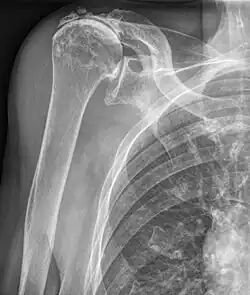

Subacromialer Raum

Als subacromialer Raum wird der Bereich unterhalb des Acromions und des Schultereckgelenkes bezeichnet. Er wird von unten durch die Rotatorenmanschette des Schultergelenkes begrenzt. Im subacromialen Raum befindet sich die Bursa subacromialis.

Einengungen des subacromialen Raumes können zum Impingement-Syndrom führen. Bei einem Riss der Rotatorenmanschette kommt es durch ein Höhertreten des Humeruskopfes zur Verschmälerung oder Aufhebung und es kann sich ein Neogelenk zwischen dem Humerus und dem Acromion ausbilden.